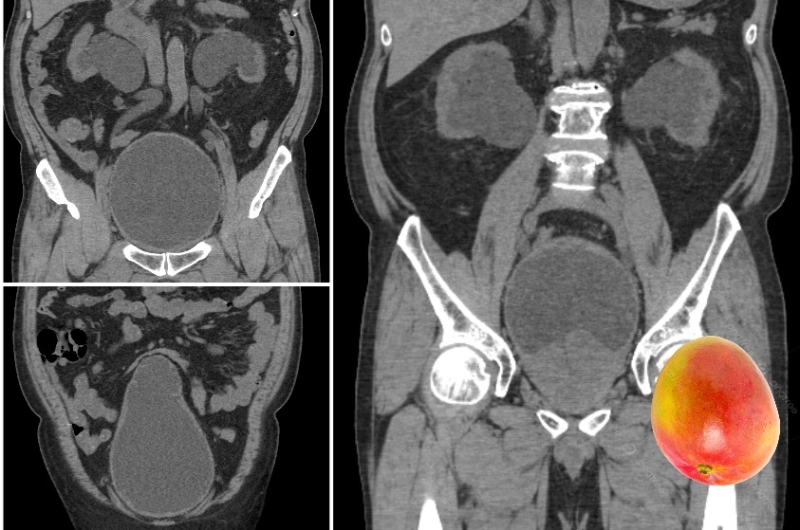

泌尿科医生吕谨亨在Facebook专页发文指,该名58岁男子早前因为容易感到疲倦而求医,经检查后发现前列腺肥大,肿如芒果;膀胱也从正常的球形,退化成圣诞树的形状。

▲该患者前列腺肥大,肿大如芒果。(图片来源:吕谨亨医生Facebook)

吕谨亨医生又指,该男子两边肾脏出现肾水肿情况,经抽血检查后发现肾功能已经受损,确诊第4期慢性肾衰竭。后来为患者放尿管,引流出约1000多毫升小便。最后,再透过手术解决前列腺肥大问题,避免肾脏和膀胱的情况持续恶化。